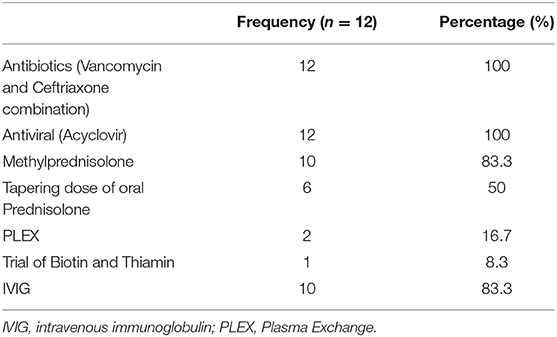

A total of 14 patients with ANEC were identified; two patients were excluded due to the inability to meet the ANEC radiological criteria. Patients' ages ranged from 10 months to 6 years (mean 30.92 months, median 22 months, standard deviation 20.63). Nine patients (75%) were female. All patients presented with preceding febrile illness in the form of upper respiratory tract infection (URTI) symptoms, or gastrointestinal symptoms in the form of vomiting or diarrhea, and altered level of consciousness. Seizures were the initial presentation in eight cases (66.7%). Brain imaging was carried out using Axial, Sagittal, and Coronal T1,T2, FLAIR, diffusion, and susceptibility weighted images which showed characteristic high signal intensity on axial T2 and FLAIR with variable degree of involvement of both thalami in all cases. Diffusion restriction was also seen, while the susceptibility sequence showed dark signal intensity with blooming, indicating hemorrhagic changes. Out of 12 patients, five (41.7%) had brainstem involvement. Follow up brain MRIs were done 2–3 months after the initial presentation, which showed signs of improvement on 33.3%, and 66.7% (n = 8) showed no signs of improvement. The clinical and radiological presentations are summarized in Tables 1, 2. Figures 1–4 show brain MRIs for selected patients.

Figure 3. Brain MRI. Axial T2 (A–C) and diffusion (D–F) showing swelling and abnormal high signal intensity of pons, bilateral external capsule, and subinsular cortex, as well as both thalami with diffusion restriction.